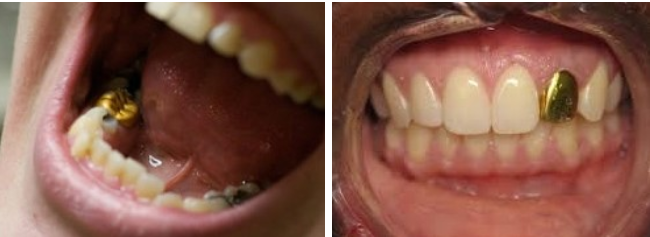

금으로 만든 보철물은 미관상좋지않아 앞니에는 사용하지않고

어금니도 꺼려하지만

연세가많으신어르신들은금을선호하시기도합니다 .

우리 인체와 가장 친화력이 있어

어금니에 시술했을 경우

편하게 사용하실 수 있습니다

금으로 보철물을 제작시 색상으로 인한 이질감이 있습니다